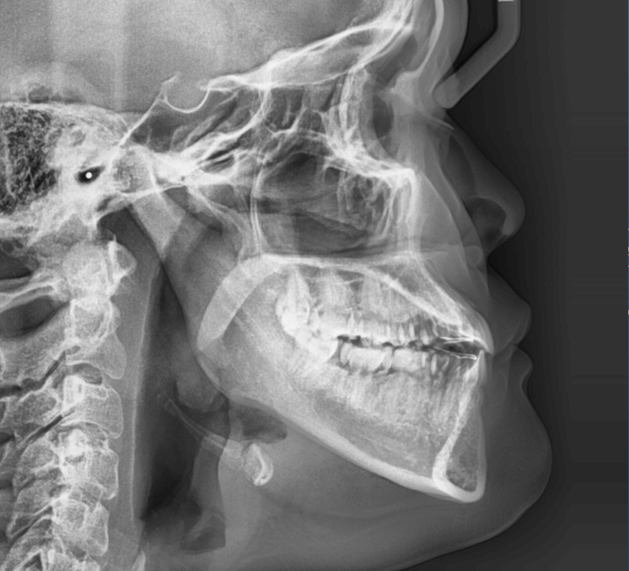

咬み合わせが逆であること(反対咬合)が気になる

| 年齢・性別 | 15歳 女性 |

|---|---|

| 主訴 | 咬み合わせが逆であること(反対咬合)を気にされて来院された女性。見た目や機能面の改善を希望されていました。 |

| 治療期間・回数 | 4年4ヶ月・28回 |

| 費用 | 900,000円 |